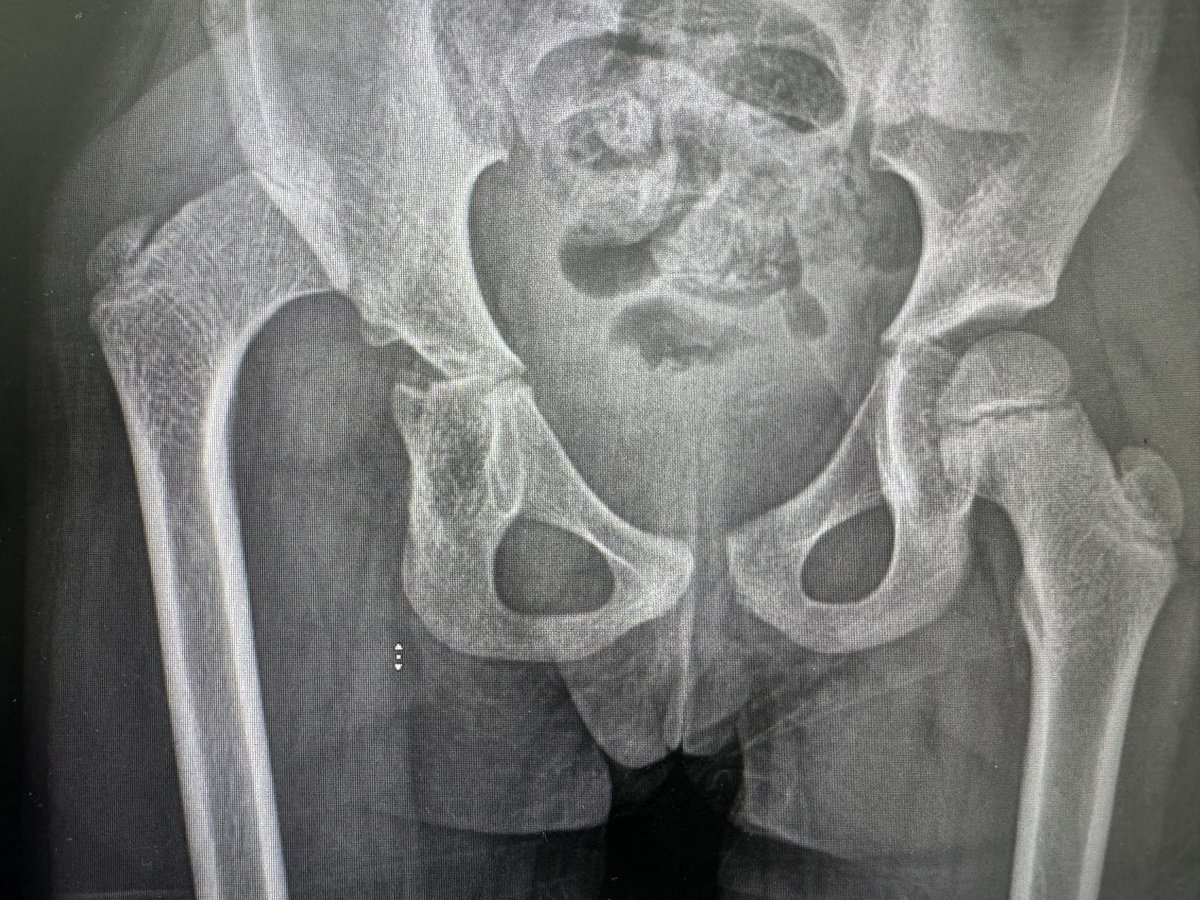

@Alaa_Albalushi ممكن يصير بعد علاج خلع الورك حتى بدون عملية، وممكن تلقائي مجهول السبب في جميع الأعمار. واحيانا بكون فيه أسباب يعرفها المختصين مثل جرعات عالية من الكورتيزون لمده طويلة.